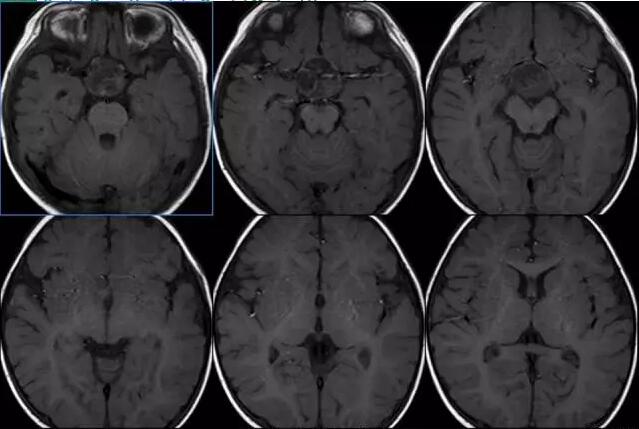

9个月大的颅咽管瘤患儿

病理诊断:颅咽管瘤

垂体瘤:本病例是特婴儿病人,病人9个多月大,累及鞍内鞍上,CT扫描病变底部边缘可见钙化影。

病变累及鞍内,垂体信号显示不清,与垂体瘤有些相似。然而垂体瘤一般发生于20岁以上成人,几乎不发生与婴幼儿和青少年。这个病人基本不考虑垂体瘤。

颅咽管瘤:多发生于鞍上,也可累及鞍内。婴幼儿和儿童病例较容易列举鞍内。病变常常出现钙化,本病例也符合,应首先考虑颅咽管瘤。

畸胎瘤:病变常出现钙化和脂肪信号。CT扫描似乎可见低密度区,但T1WI未见脂肪高信号,可除外病变内脂肪信号。病变钙化特点虽然更分会颅咽管瘤,但也不能完全除外畸胎瘤,可以在第二位考虑。

星形细胞瘤:通常为长T1长T2信号影,钙化很少,也可不考虑。

生殖细胞瘤:病人通常以多以多尿起病,病变通常有弥散受限。与本病例也不一致,故不考虑。